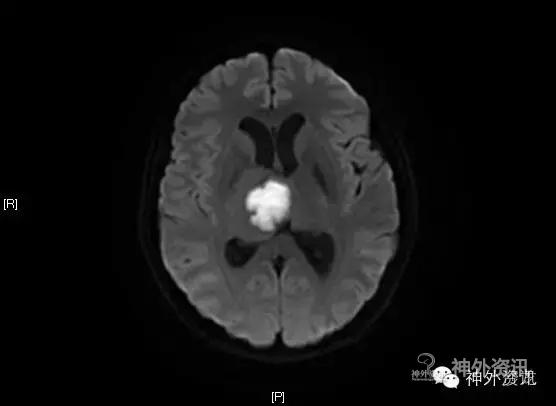

CT头胸部平扫:右丘脑占位,考虑胶质瘤可能,建议进一步检查。左侧基底节区腔梗右下肺感染;左肺上叶舌段异常改变,考虑为畸形血管可能,必要时增强检查两侧胸腔少量积液。

MRI:右侧丘脑占位,考虑胶质瘤可能性大(Ⅲ-Ⅳ级),病灶累及中脑右侧大脑脚,轻度脑积水;不除外转移瘤可能,请结合相关病史及检查。

影像学检查: